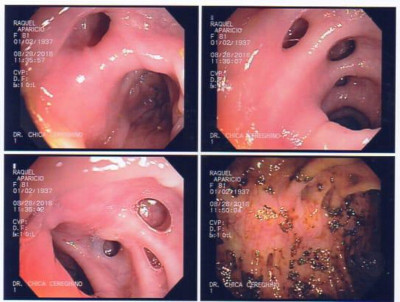

Paciente con cáncer gástrico